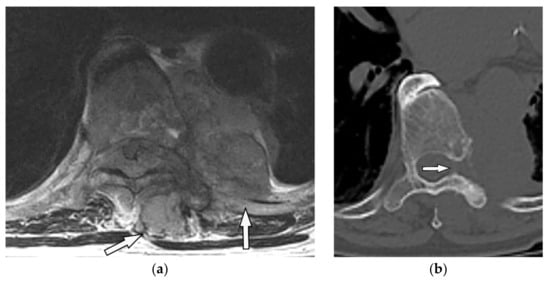

9.1.1. Schwannoma

Schwannoma is an encapsulated slow-growing peripheral nerve sheet neoplasm typically occurring in patients between 20–50 years old [6,16]. Chest wall schwannomas arise from spinal nerve roots with a dumbbell shape appearance and extend through the course of intercostal nerves, paravertebral region, or spinal canal [7,43].

Schwannoma presents a well-defined homogenous mass on CT scan with attenuation similar or less than muscle. The “Fat-split” sign caused by adjacent surrounding fat is indicative of its non-infiltrating growing pattern. It also shows remarkable post-contrast enhancement except for areas of necrosis or cystic changes (Figure 14). On MR images, it has intensity equal to or slightly more than muscle on T1-weighted and marked hyperintensity on T2-weighted images. Scalloping or bony erosions might be the only radiographic manifestations reflecting its benign nature [6,7,16,43].

9.1.2. Neurofibroma

Neurofibroma is another slow-growing peripheral nerve sheet neoplasm that affects patients in their 20s to 30s with equal male and female prevalence. Localized Neurofibroma, which includes approximately 90% of cases, is not typically associated with neurofibromatosis type 1 (NF1). However, the majority of cases with plexiform type have underlying NF1 [7,16].

The main CT findings are well-circumscribed mass with smooth margin, soft tissue attenuation, possible internal calcifications, and adjacent rib erosion. Neural foraminal widening secondary to tumor extension can be accurately identified on multidetector CT (Figure 15). “Target sign” appears on both T2-weighted and gadolinium-enhanced MR images. It is related to the peripheral abundant stromal matrix surrounding the high cellular center, presenting as hyperintense rim and hypointense center, respectively (Figure 16 and Figure 17) [7,16,43].